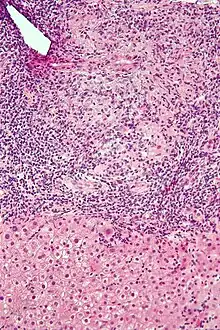

Histology of primary biliary cholangitis × 200 liver biopsy -

On microscopic examination of liver biopsy specimens, PBC is characterized by chronic, non-suppurative inflammation, which surrounds and destroys interlobular and septal bile ducts. These histopathologic findings in primary biliary cholangitis include the following:[34]

- Inflammation of the bile ducts, characterized by intraepithelial lymphocytes, and

- Periductal epithelioid granulomata.

- Proliferation of bile ductules

- Fibrosis (scarring)

The Ludwig and Scheuer scoring systems have historically been used to stratify four (1–4) ‘stages’ of PBC, with stage 4 indicating the presence of cirrhosis. In the new system of Nakanuma, the stage of disease is based on fibrosis, bile duct loss and features of cholate-stasis, i.e. deposition of orcein-positive granules, whereas the grade of necroinflammatory activity is based on cholangitis and interface hepatitis. The accumulation of orcein-positive granules occurs evenly across the PBC liver, which means that staging using the Nakanuma system is more reliable regarding sampling variability.